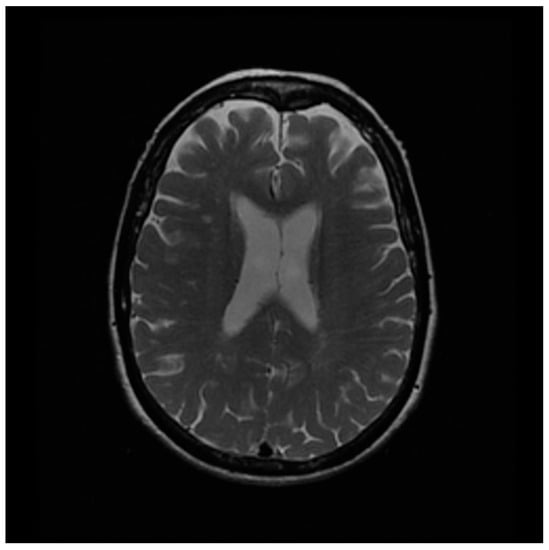

3.2. Clinical Study